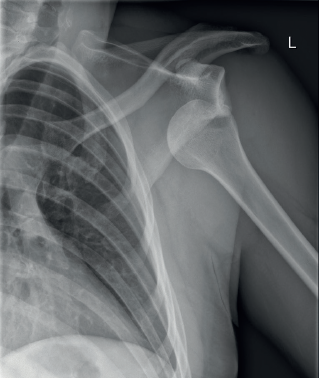

Varón de 22 años, el cual se presenta a urgencias por caída sobre su plano de sustentación y traumatismo sobre hombro izquierdo que condiciona pérdida de la morfología del hombro, con signo de charratera, dolor intenso y brazo en posición antiálgica, brazo en posición ligeramente abducida, incapacidad de tocar el hombro derecho con la palma de la mano izquierda, ligero déficit neurológico del nervio axilar. Por lo que se solicitan radiografías de vista anteroposterior, axilar lateral y escapular Y.

1. De acuerdo con el cuadro clínico y la figura 1, ¿cuál es tu sospecha diagnóstica

1. Luxación posterior de hombro.

2. Luxación anterior de hombro.

3. Luxación subcoracoidea.

4. Luxación acromioclavicular.

Figura 1 Radiografía anteroposterior de hombro?

3. ¿Qué hallazgos radiológicos se observan en la imagen radiográfica?

1. Fractura de la cabeza humeral.

2. Desplazamiento posterior de la cabeza humeral con fractura de la glenoides.

3. Pérdida de la congruencia acromioclavicular.

4. Desplazamiento anteroinferior de la cabeza humeral.

4. ¿Cuál es el porcentaje de incidencia de esta patología?

1. 90-95%.

Respuestas correctas: 1: b; 2: b; 3: d; 4: a; 5: b.